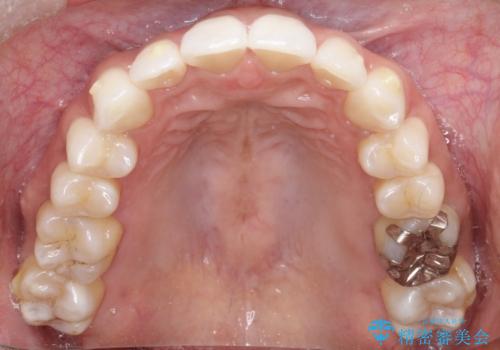

【インビザライン】前歯の凸凹をIPRで改善

- 前歯の凸凹を主訴に来院されました。

前歯を並べるために歯と歯の間にヤスリを入れてわずかに歯を削ることでスペースを確保しています。

歯と歯の間にヤスリを入れてわずかに歯を削ることでスペースを確保する処置をIPRと呼びます。

当院では拡大鏡を用いて丁寧に処置することで歯冠形態を損なわずに行うことができます。